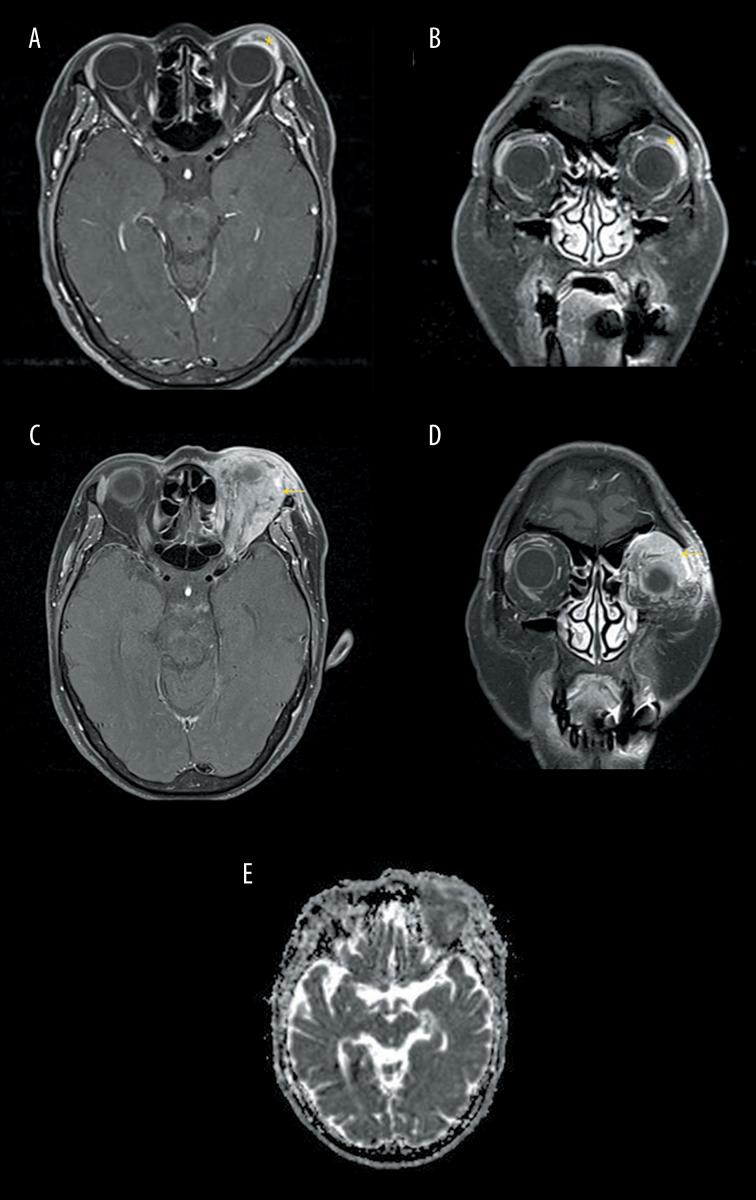

BACKGROUND Kimura disease is a rare, chronic inflammatory disorder typically presenting as a painless mass in the head or neck and associated with elevated serum immunoglobulin E and blood and tissue eosinophilia. Generally benign, its management is not well-defined, but corticosteroids are a common initial treatment. We detail a case of refractory Kimura disease successfully managed with CVP (Cyclophosphamide, Vincristine, Prednisone) chemotherapy and no recurrence during 6 rounds of treatment. CASE REPORT A 64-year-old woman, previously diagnosed with Kimura disease, returned to the hospital with upper eyelid ptosis. Upon examination, a solid mass was palpable in her left upper eyelid. Peripheral blood tests confirmed elevated IgE levels at 356.0 IU/ml. An excisional biopsy showed infiltration of lymphocytes and eosinophils, consistent with Kimura disease. Despite undergoing corticosteroid treatment, surgical debulking, radiation, and immunosuppressant therapy, her condition worsened. Concerns were raised due to imaging features suggestive of lymphoma, although no malignancy was evident in subsequent biopsies. It was decided to manage the disease using CVP chemotherapy, leading to significant symptom improvement. There have been no recurrences during the 12-month follow-up period. CONCLUSIONS Kimura disease is typically benign and responsive to treatment, but it often recurs and can progress. When symptoms are not controlled with conventional treatments, including corticosteroids, immunosuppressants, radiation, and surgical debulking, chemotherapy may be a reasonable option even when no definite signs of malignancy is identified. Further research is needed to explore the utility of CHOP and CVP in managing uncontrolled Kimura disease.

一名 64 岁女性,曾被诊断为木村病,因上眼睑下垂返回医院。检查时,可触及其左眼上眼睑有一实性肿块。外周血检查证实 IgE 水平升高至 356.0 IU/ml。切除活检显示淋巴细胞和嗜酸性粒细胞浸润,符合木村病。尽管接受了皮质类固醇治疗、手术去瘤、放疗和免疫抑制剂治疗,但病情仍恶化。由于影像学特征提示淋巴瘤,引起了关注,尽管随后的活检未发现恶性肿瘤。决定使用 CVP 化疗来治疗这种疾病,导致症状显著改善。在 12 个月的随访期间,没有复发。